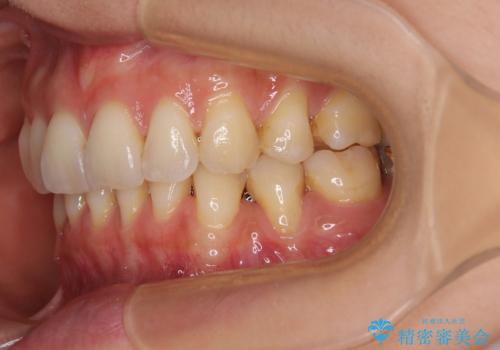

- 歯肉が薄く、退縮して露出した歯根を気にして来院された患者様です。

元々歯肉が非常に薄いことが推察され、抜歯矯正による移動が大きかったのか、歯肉が退縮している状態でした。